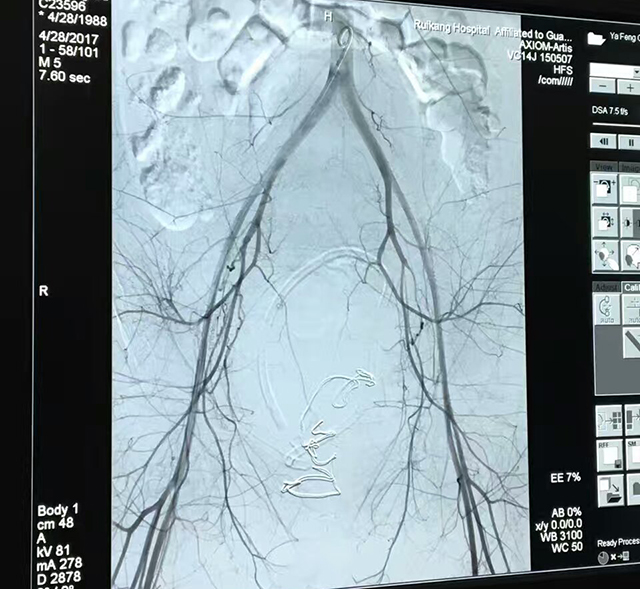

玉华医生介绍,牙女士在4月28日12点16分通过剖宫产分娩出一健康男孩,但由于子宫收缩欠佳,出现了术后大出血的状况。病情严重而紧急,产科苏莉主任立即组织医疗团队及其他相关部门联合抢救。抢救期间出血状况虽得到控制但仍出现几次反复,最后在介入科的共同努力下行子宫动脉栓塞+双侧髂内动脉栓塞术才终止了出血状况,抢救成功。牙女士在抢救八个小时后转危为安。

玉医生介绍,这是我院产科首次运用子宫动脉栓塞术成功治疗了难治性产后出血,这种新的介入治疗技术可应用在很多妇产科疾病中,尤其对产后出血、前置胎盘出血、瘢痕妊娠等临床棘手的、高风险的疾病,损伤小,止血效果确切肯定,既避免了二次手术的危险性,又能为患者保全子宫,保留生育能力。

目前针对产后出血的救治的方法有传统的按摩压迫子宫、加强子宫收缩药物、各种缝合,甚至子宫切除等,近年来成功运用子宫动脉栓塞术,髂内动脉栓塞术等技术到产后出血的救治中,疗效显著,逐步成为治疗难治性产后出血的核心技术。

介入治疗